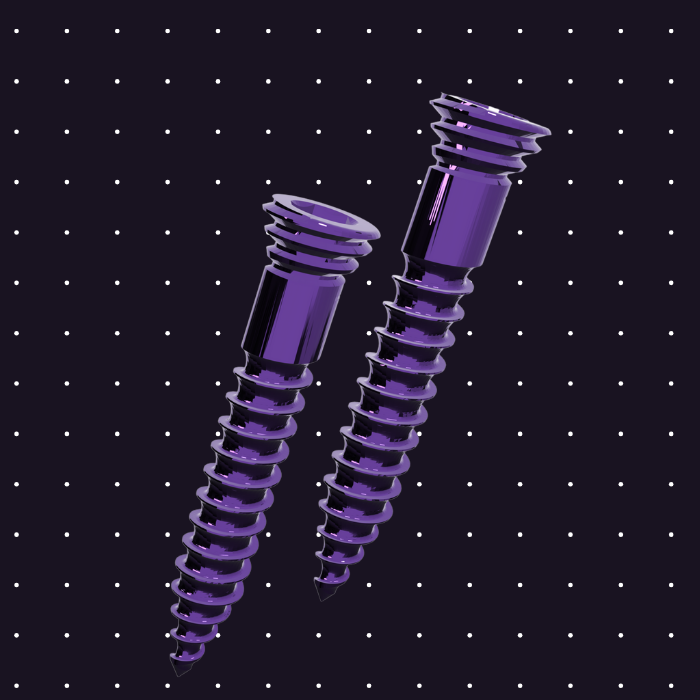

MARPE Mini-İmplantlar

Yönlendirici yiv (guiding thread) özellikli, lazer kaynak ve lazer sinter ile üretilmiş premium mini-implantlar. Açı hatası önleme teknolojisi ile doğru yerleşim garantisi.

- 8-12 mm uzunluk seçenekleri

- 1.8-2.0 mm çap

- Yönlendirici yiv teknolojisi

- Açı hatası önleme ve paralellik garantisi